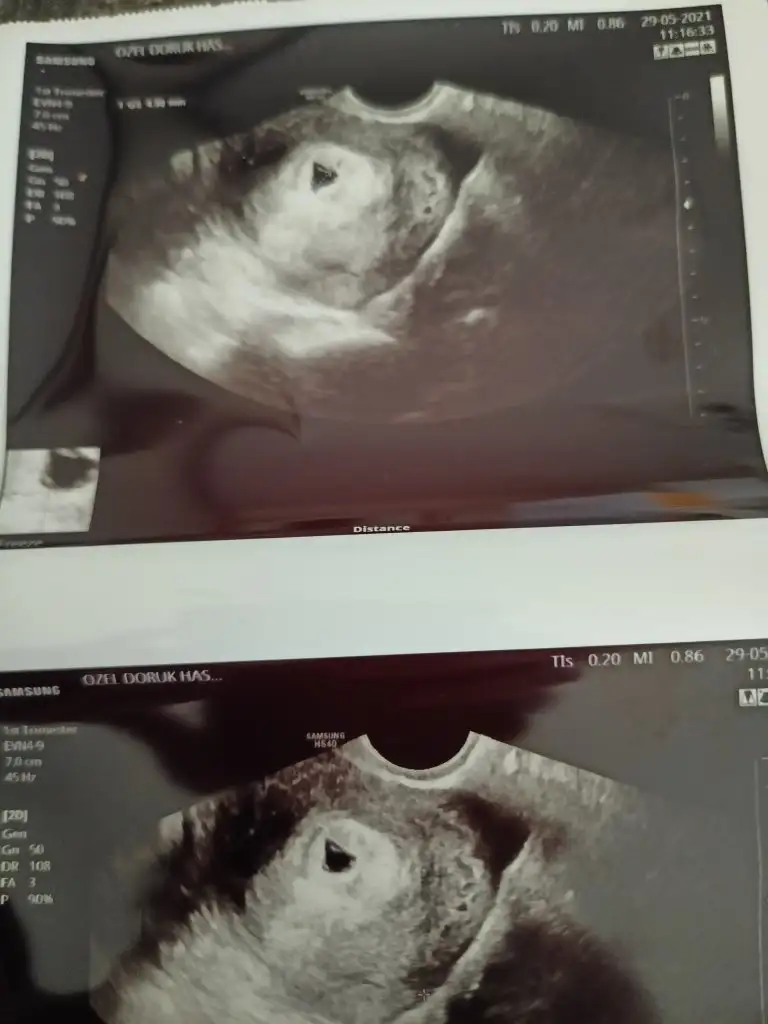

Günaydın kizlar bu gün Dr randevum vardi kese alttan muayene ile göründü Dr kese düzensiz dusukte olabilir duzelebilirde dedi kanamalı alan varmış ama benim kanamam yok